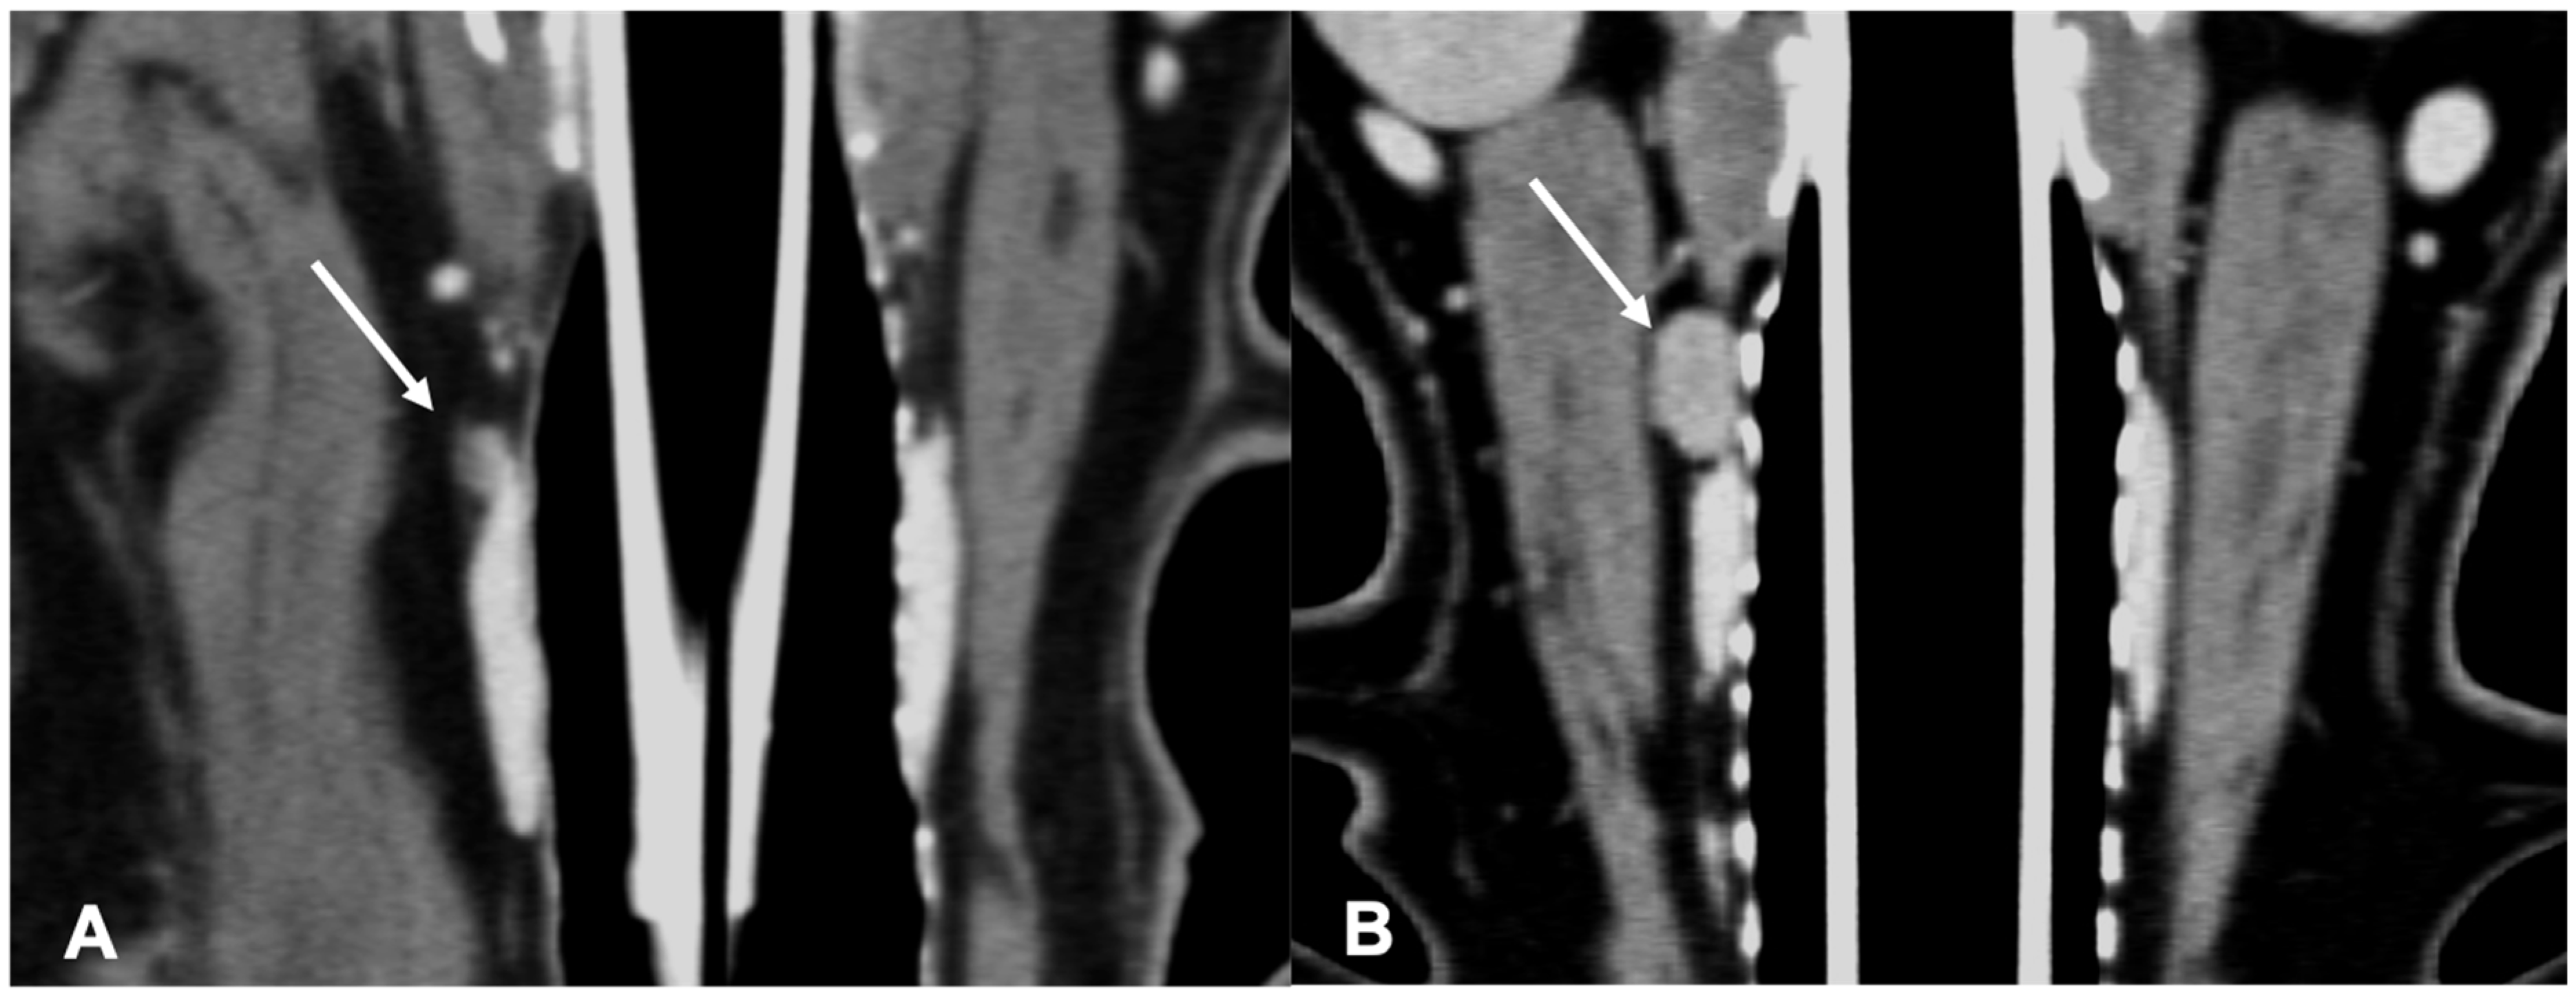

The adenomas were mainly ovoid in shape (58%) and with homogeneous enhancement (67%) (Figure 3).

Figure 3.

CT appearance of parathyroid gland adenoma. Post-contrast dorsal CT reconstruction in two dogs with parathyroid gland adenoma (arrow) at the level of the right external parathyroid. Note the rounded (A) and ovoid (B) shape; in both cases the parathyroid adenoma is hypoattenuating with respect to the thyroid tissue and homogenously enhancing.

The adenocarcinomas (Figure 4) showed variable shape and enhancement, with half of the cases showing homogeneous enhancement and half showing heterogeneous enhancement after contrast administration.

Figure 4.

CT appearance of parathyroid gland adenocarcinoma. Post-contrast dorsal CT reconstruction in two dogs with parathyroid gland adenocarcinoma (arrow) at the level of the left external parathyroid. Note the variable CT appearance: large size of the lesion in (A) showing heterogeneous contrast enhancement; the adenocarcinoma in (B) is smaller, has a rounded shape, and homogeneous contrast enhancement.